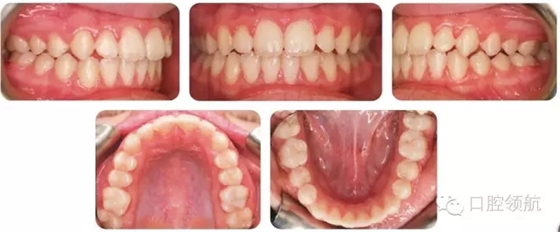

考慮拔牙牙位時(shí),一般會(huì)選擇多生牙;但也要仔細(xì)評(píng)估正常牙和多生牙的冠根解剖,再?zèng)Q定拔牙牙位。這個(gè)病例中,更靠遠(yuǎn)中的側(cè)切牙(多生牙)被拔除。圖2.2是經(jīng)過(guò)功能矯治和固定矯治后的最終口內(nèi)像。

圖2.2